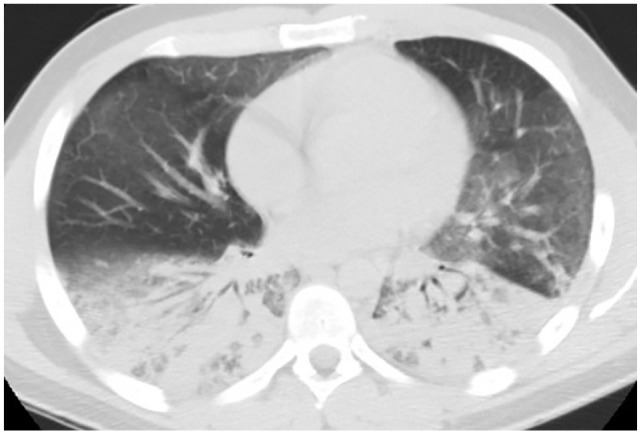

1). Urine drug screen was positive for cannabinoids/THC. Extensive infectious workup including sputum studies, urine, and serum studies were negative (Table 1). CXR showed bilateral air space disease and CT of the chest without contrast showed bilateral upper lobe ground glass opacities and lower lobe dense consolidations (Figure 2). Ultrasound of the abdomen was unremarkable. Supportive care was provided by oxygen supplementation via high-flow nasal cannula to maintain saturations above 90%. He was initiated on methylprednisolone 60 mg intravenously (IV) twice a day for presumed VALI. He was discharged home with 2 L of supplemental oxygen via nasal cannula on prednisone 40 mg daily with a 3-week steroid taper regimen.